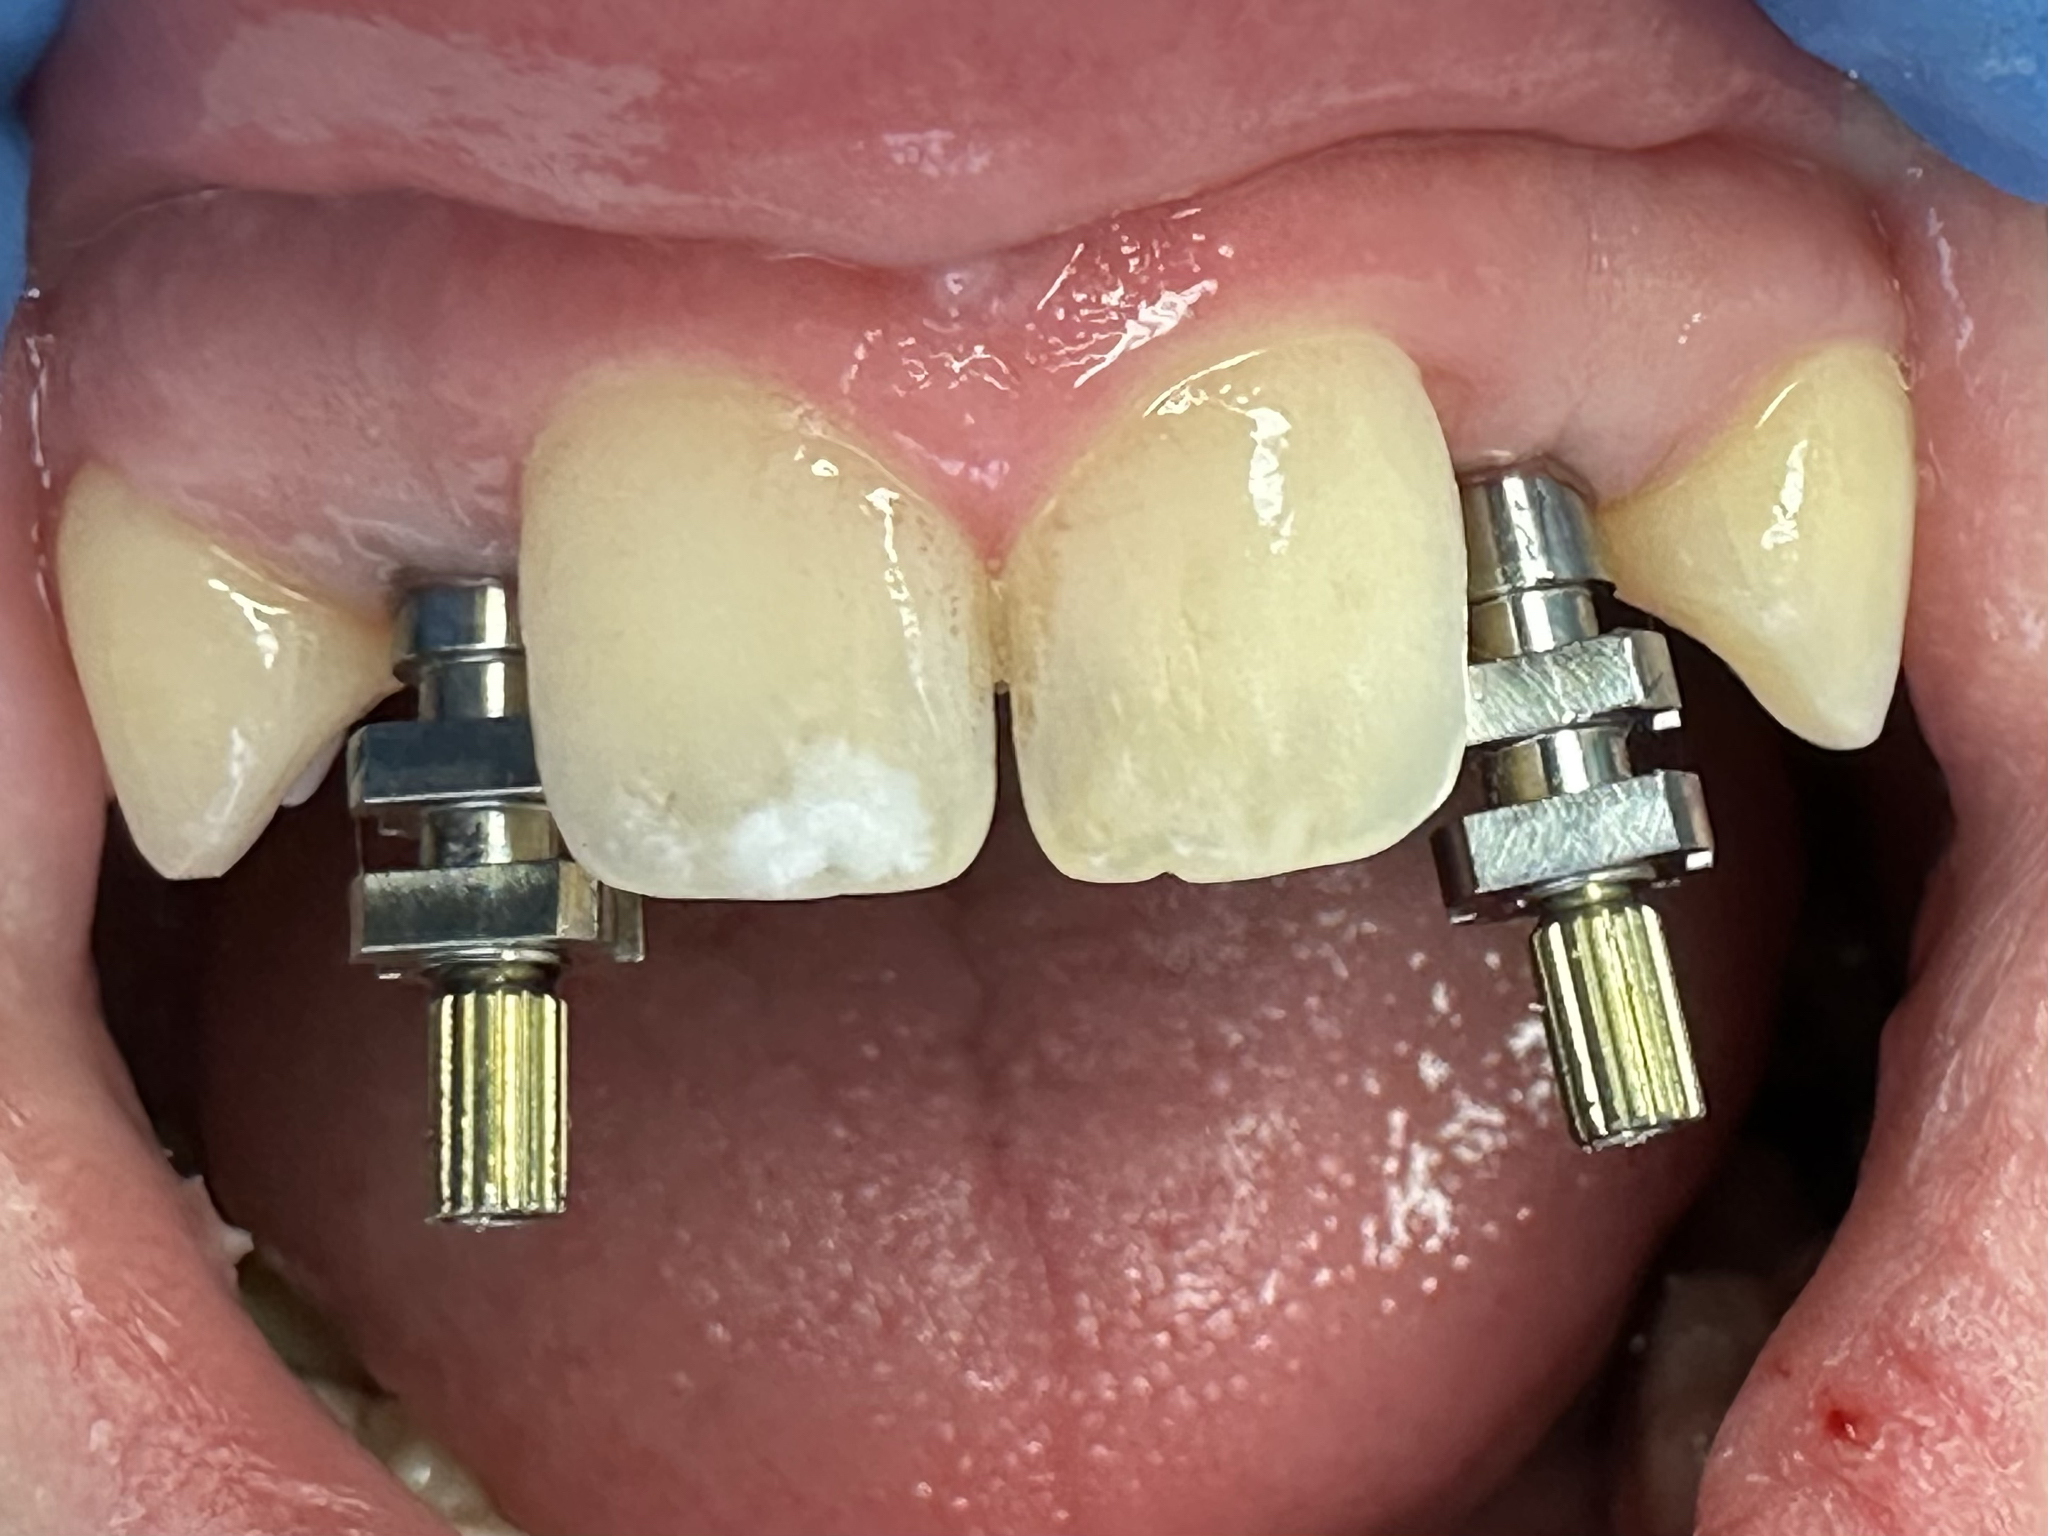

Case Study: Dental Implant

A patient with a missing tooth received a dental implant, restoring both function and aesthetics.